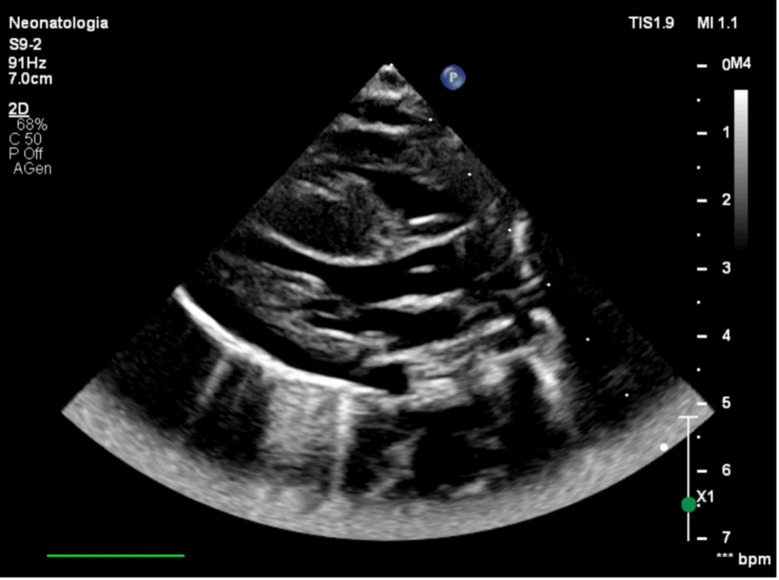

Case presentation: We present a case report of a male infant, inborn and delivered at a gestational age of 39 weeks. Medical history reveals consanguineous parents with no invasive screening tests performed during pregnancy. They chose not to undergo prenatal screening even though they were aware of the risks associated with their consanguinity. At birth, the newborn was atonic and pale, with a heart rate of 70 bpm. During resuscitation, an umbilical venous catheter was placed, and three doses of adrenaline and one dose of bicarbonate were administered. At the Neonatal Intensive Care Unit, he underwent therapeutic hypothermia. Echocardiography, performed a few hours later, revealed severe biventricular and septal hypertrophy consistent with non-obstructive hypertrophic cardiomyopathy. During recovery, even after the discontinuation of hypothermia, the newborn exhibited abnormal neurological signs, including axial hypotonia and a tendency to keep his mouth open with tongue protrusion. Given the clinical picture and the early detection of septal and biventricular hypertrophy, genetic testing was performed, revealing a homozygous c.2560 C > T variant in the acid alpha-glucosidase gene (both parents were carriers), described in scientific literature as a class 5 pathogenic variant associated with glycogenosis type II (Pompe disease).